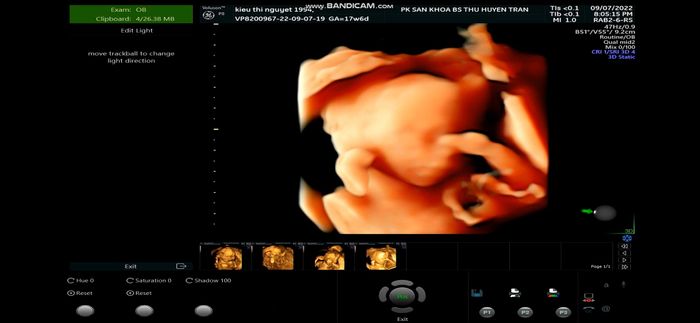

Phòng khám sản phụ khoa của Ths. Bác sĩ Thu Huyền Trần là một trong những địa chỉ uy tín và chất lượng hàng đầu tại Hà Nội, được Sở Y tế cấp phép hoạt động. Nơi đây thu hút rất nhiều mẹ bầu nhờ dịch vụ tận tình, thường xuyên có đông đúc người chờ đợi để được khám.

- Ths. Bs. Trần Thị Thu Huyền, bác sĩ chính của phòng khám, hiện công tác tại khoa sản - Bệnh viện Bưu Điện với hơn 10 năm kinh nghiệm điều trị trực tiếp.

- Tại phòng khám, mẹ bầu sẽ được thực hiện đầy đủ các siêu âm, xét nghiệm cần thiết dựa trên tiền sử bệnh lý và tình trạng sức khỏe từng giai đoạn.

- Trang thiết bị hiện đại, đầy đủ như máy siêu âm 2D, 4D, xét nghiệm nước tiểu, và hệ thống máy móc xét nghiệm chính hãng đảm bảo an toàn và cung cấp đa dạng dịch vụ cho mẹ bầu.